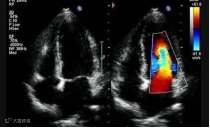

体检做心脏彩超检查,

经常有报告“左室舒张功能减低”,

我们先看下心脏的左室是怎么工作的:

左心室先舒张,将富含氧气的血液从左心房汲入左心室,然后再收缩、将新鲜血液泵至主动脉,再由主动脉逐级输送全身。

这样,左心室就像水泵把水从水池里泵到别的地方一样,通过收缩-舒张-收缩-舒张这一系列过程,将新鲜血液供应至全身。

左室舒张功能减低,就是左心室从左心房汲血的功能下降了,类似水泵从水池吸水的功能下降了。